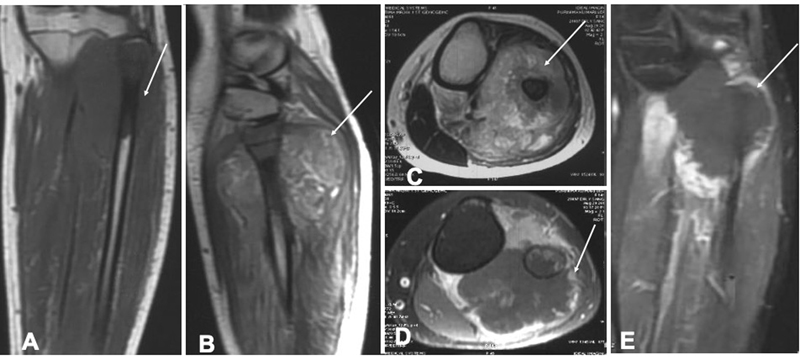

A 17-year-old female initially presented with pain and swelling in the left calf for 1 month. Initial evaluation with magnetic resonance imaging (MRI) of the lower limb ( [Fig. 1A–E]) showed a heterogeneous lesion in both T1-weighted and T2-weighted images at the left upper fibula with surrounding peripheral enhancing soft tissue lesion (70 × 63 × 63mm) and medullary changes that suggested the radiological possibility of osteosarcoma, Ewing's sarcoma, or chronic osteomyelitis. Histopathology findings on biopsy showed the tumor cell had hyperchromatic pleomorphic nucleoli with a high nuclear/ cytoplasm ratio and a moderate amount of cytoplasm. The tumor showed overall areas of necrosis (80–90%) with few areas of chondroblastic differentiation with features consistent with conventional osteosarcoma. CT chest was done for metastatic screening and found to be normal. The patient was started on neoadjuvant ifosfamide, doxorubicin, cisplatin protocol followed by surgery and adjuvant chemotherapy within 8 months. She had developed ifosfamide encephalopathy during chemotherapy post the eighth cycle, following which further chemotherapy was withheld. She was on regular follow-up, doing fine for the next year and CT chest was normal. The patient started having dull aching, right temporal headache after 1 year of the last cycle of chemotherapy for which she was evaluated with CT scan in a local hospital, which showed a neoplastic mass in the right cerebral hemisphere causing a mass effect with midline shift to the left side ([Fig. 2A]). MRI was performed after 20 days of symptom onset showed a right supratentorial mass lesion in the right posterior temporal lobe with internal bleeding and peripheral enhancement, mass effect with midline shift. The lesion was T1 hypointense with focal areas of hyperintensities, T2 hyperintense with fluid–fluid level, multiple areas of blooming on susceptibility-weighted imaging, and without restriction on diffusion-weighted imaging ([Fig. 2B-E]). Elevated perfusion was seen within the lesion and irregular shaggy enhancement on the postcontrast study ([Fig. 2F, G]). No soft ossification or calcification was seen on phase images. With these constellations of findings, an imaging diagnosis was made of high-grade glioma. The second possibility was osteosarcoma metastasis, as known primary was osteosarcoma of fibula but was confounded by the absence of other metastatic areas and no calcification within the tumor mass. She was admitted to the oncology department and evaluated with positron emission tomography-computed tomography, which showed remission in the primary carcinoma site, with no other metastatic lesion anywhere in the body. Neurosurgery opinion was taken and was they advised for surgery as the tumor was quite big with radiological features suggestive of a high-grade tumor. Right frontotemporal craniotomy and gross total excision of the tumor were done. Intraoperative findings showed an intra-axial firm to hard whitish solid cystic lesion arising from the right lateral ventricle and extending to the temporal base, invading the pial surface. The tumor was dissected circumferentially in a piecemeal fashion and excised with no gross residual disease. Histopathology of the resected lesion showed a tumor in the right lateral ventricle extending to the temporal lobe comprised of multiple firm-to-hard tissue pieces measuring 9 × 8 × 1cm. Microscopy sections examined showed that the tumor was composed of spindle cells, mitosis, and areas of necrosis with lacy osteoid formation and a few chondroblastic areas ([Fig. 2H]). The above features were suggestive of metastatic osteosarcoma. The patient was symptomatically better after the procedure, and was further planned for methotrexate, ifosfamide, and etoposide.

| Figure 2: Magnetic resonance imaging of the brain showing the metastatic lesion within the brain. Axial noncontrast computed tomography head (A) showed a large heterogeneous solid cystic lesion with internal areas of hemorrhage and without calcification in the right posterior temporal lobe (arrow). Axial T2-weighted (B), axial susceptibility-weighted imaging (C), axial T1 (D), and axial diffusion-weighted imaging (E) showed a large solid cystic multiloculated lesion (arrow) with the fluid–fluid level in the right posterior temporal lobe with internal blooming and without restriction. T2* perfusion (F), and axial T1 phase-contrast (G) showed elevated perfusion and irregular shaggy enhancement with nodularity (arrow). Photomicrograph (H) showed malignant mesenchymal tumor exhibiting pleomorphism and hyperchromasia with osteoid matrix production.